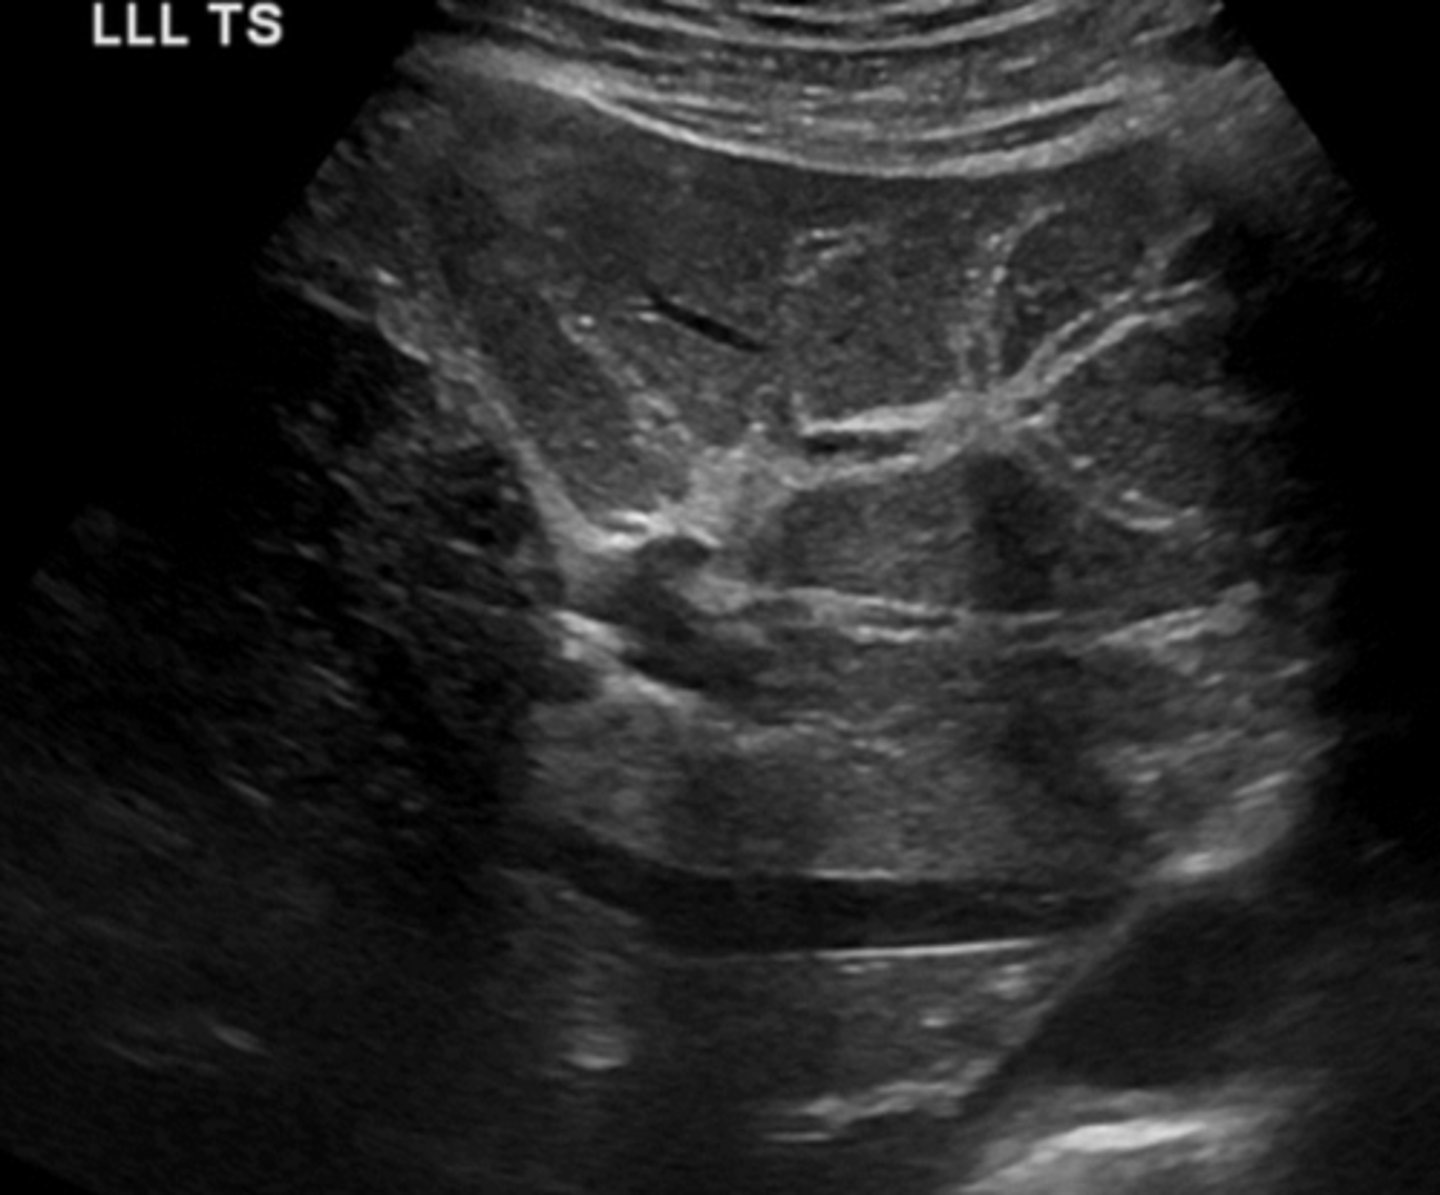

True Cyst Sonographic Appearance

-round to oval

-smooth

-thin, well defined walls

-anechoic

-w/ posterior enhancement

-may be multilocular

-be sure to differentiate from fluid (surrounding GI structures)

True Cyst